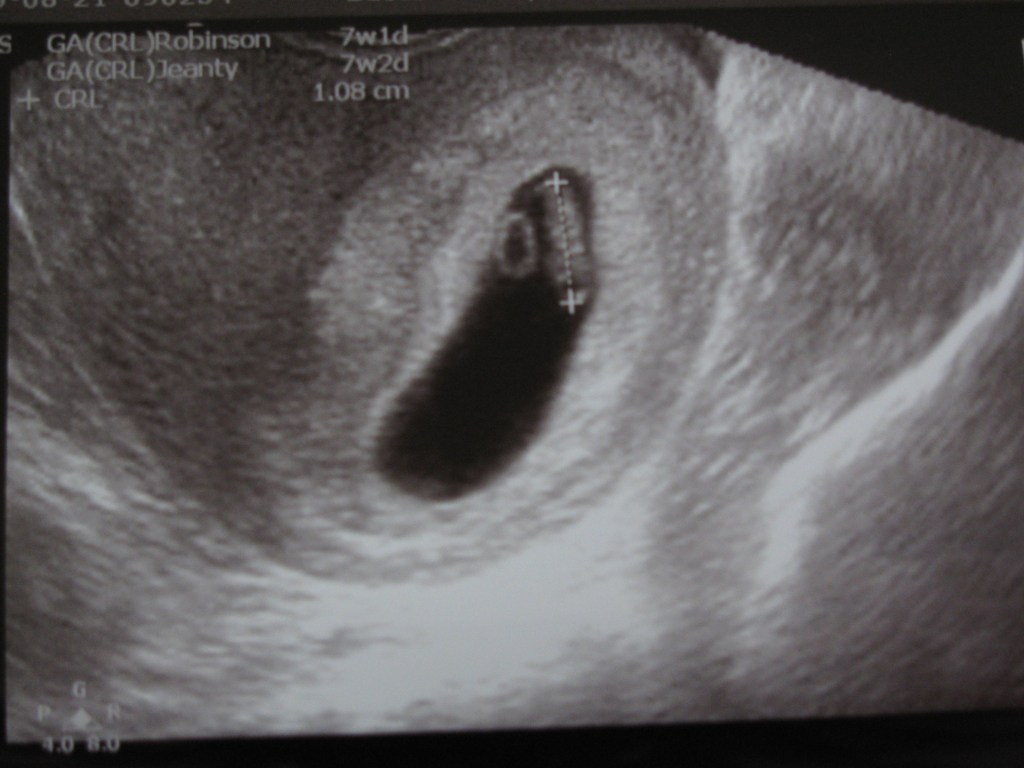

Pictures of the first glimpse of our second cute baby: